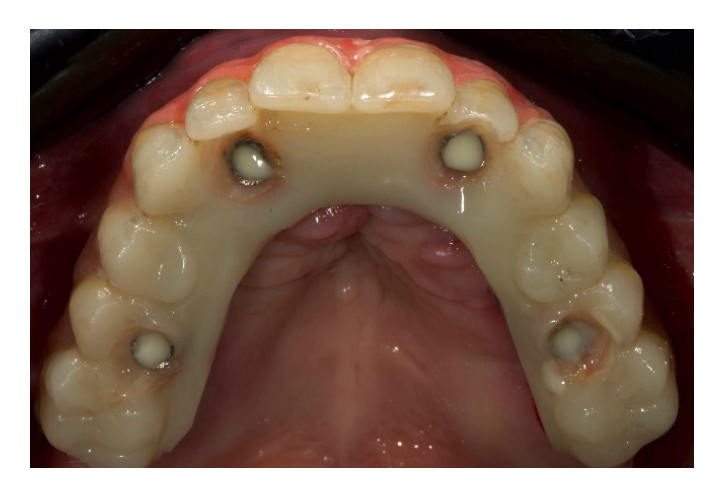

Ниже представлен объяснительный клинический случай. 62-летняя женщина обратилась за вторым мнением из-за существующих съемных частичных протезов, закрепленных на оставшихся естественных элементах, которые были установлены несколько месяцев назад. При клиническом и рентгенологическом обследовании пациентка предъявила основные жалобы на подвижность зубов, кровоточивость десен, боль, дискомфорт, плохую функцию и неэстетичный внешний вид (Рисунки 1 и 2).

Диагностическая терапия была направлена на переобучение пациента, который был беззубым в течение нескольких лет. Были запланированы немедленные, диагностические, полные съемные верхние и нижние протезы. Этот первый этап был полностью аналогичным. Предварительные слепки были сняты с помощью альгината для отливки учебных моделей. Окончательные слепки были сняты с помощью индивидуального ложки для слепков. Центрическая связь и вертикальное измерение окклюзии были зафиксированы с использованием маневра Досона и фонетических звуков соответственно. Мастермодели были установлены в полу-регулируемом артикуляторе с помощью лицевой дуги. После этого немедленный съемный протез был завершен с использованием задних зубов с углом наклона бугорков 0 градусов, чтобы позволить перемещение нижней челюсти. В день первой операции пациенту была проведена местная анестезия (4% артикаин с адреналином 1/100,000, Septanest, Septodont, Матаро, Испания). Все оставшиеся зубы были аккуратно удалены, и костный гребень был моделирован. Немедленный, диагностический, полный съемный протез был затем передан. Основание и окклюзия были отрегулированы, и пациент наблюдался каждые две недели в течение четырех месяцев. На каждом осмотре окклюзия регулировалась для нахождения правильного положения нижней челюсти, без изменения вертикального измерения окклюзии. Через четыре месяца пациент был доволен новой функцией и эстетикой. Следующим шагом было планирование установки имплантатов, ориентированных на протезирование. Существующие, диагностические, функционализированные съемные протезы были дублированы и использованы в качестве индивидуальных ложек для слепков для снятия новых окончательных слепков. Для установки мастермоделей и дубликатов в артикуляторе использовалась техника перекрестного монтажа, сохраняя центровую связь и актуальное вертикальное измерение окклюзии. Наконец, новые временные протезы были изготовлены с полностью анатомической окклюзией (Рисунок 3). На этом этапе была обеспечена двусторонняя сбалансированная окклюзия у всех леченых пациентов.